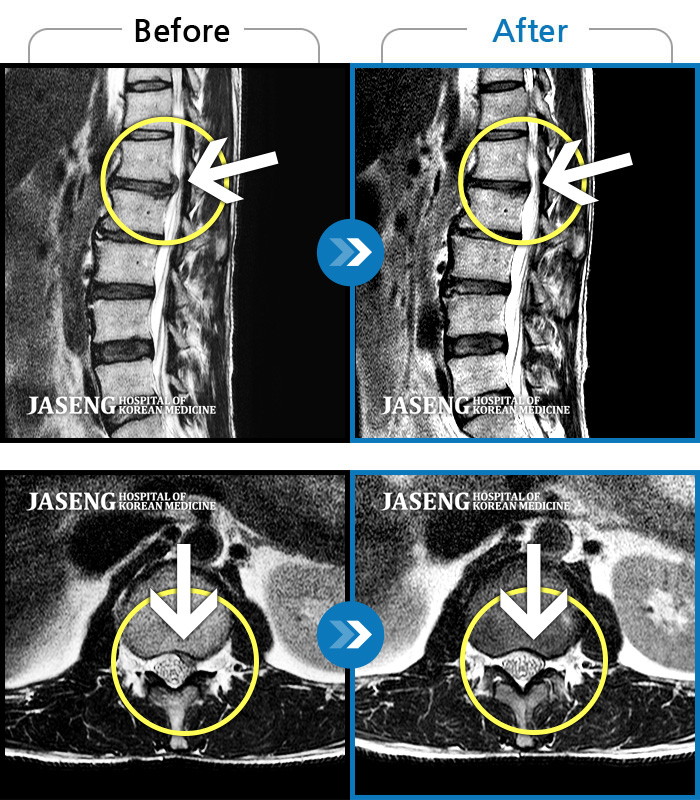

Before

After

처음 내원시 허리 통증이 심하여 일상생활에 불편감이 있으신 환자분이셨습니다.

2023.10.03 ~ 2025.03.22